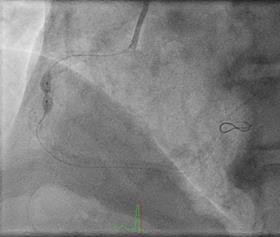

Can thiệp ngã ba động mạch liên thất trước và nhánh chéo 1 với hai stent có bọc thuốc bằng kĩ thuật cullote. Tiếp tục can thiệp động mạch vành phải với ống thông can thiệp (guiding catheter) (Cordis JR4 cm 6Fr) và dây dẫn (Asahi Sion 0.014”). Nong tổn thương bằng bóng 3.5 x 15mm (Neich Sapphire), bóng 4.0 x 12 (NC Quantum Apex), bóng cắt 3.5 x 15 (Cutting balloon, Angiosculpt) không làm vỡ được mảng vữa xơ. Quyết định dùng hệ thống khoan cắt mảng vữa xơ với dây dẫn mềm (Boston Scientific Rotablator Rotalink Plus) và mũi khoan (burr) 1.5mm. Tuy nhiên vì kích thước động mạch quá lớn nên mũi khoan đi qua tổn thương mà không chạm vào mảng vữa xơ được. Chuyển sang mũi khoan có đường kính lớn hơn 2.15mm với tốc độ khoan 150000 vòng /phút. Khi mũi khoa đi qua được 1/3 tổn thương thì không thể di chuyển được tiếp. Nhận định tại thời điểm đó là mũi khoan bị kẹt trong tổn thương tại đoạn giữa của động mạch vành phải. Ngay lập tức các bác sỹ có kinh  nghiệm can thiệp trong bệnh viện được mời đến phòng can thiệp đồng thời thông báo cho các phẫu thuật viên tim mạch chuẩn bị trong trường hợp cần thiết. Bệnh nhân có biểu hiện đau tức ngực trái, tuy nhiên mạch và huyết áp tương đối ổn định, điện tim không thay đổi. Dòng chảy trong động mạch vành còn duy trì nhưng chậm TIMI 2. Sau khi hội ý, hướng xử trí đầu tiên là dùng dây dẫn cứng Conquest Pro (Asahi) để đi qua tổn thương nhưng không thành công. Sau đó chúng tôi quyết định cắt đoạn đầu của hệ thống nối mũi khoan, đưa ống thông heartrail (Terumo) sát vào mũi khoan nhằm thay đổi tư thế và cố định mũi khoan vào dây dẫn để đưa ra ngoài. Cuối cùng mũi khoan được đưa ra ngoài thành công. Tổn thương tiếp tục được nong bằng bóng cắt và bóng áp lực cao và đặt được giá đỡ kim loại (stent) bọc thuốc 4.0 x 26mm. Kết quả là động mạch vành được mở rộng hoàn toàn, bệnh nhân không còn đau ngực, huyết động ổn định.

Hình 1: A- hình ảnh động mạch vành trước can thiệp; B - dùng bóng cắt (cutting balloon) không phá vỡ được cấu trúc mảng vữa xơ; C – mũi khoan 1.5 không chạm vào được mảng vữa xơ vôi hóa; D – mũi khoan 2.15 bị tắc tại vị trí hẹp.